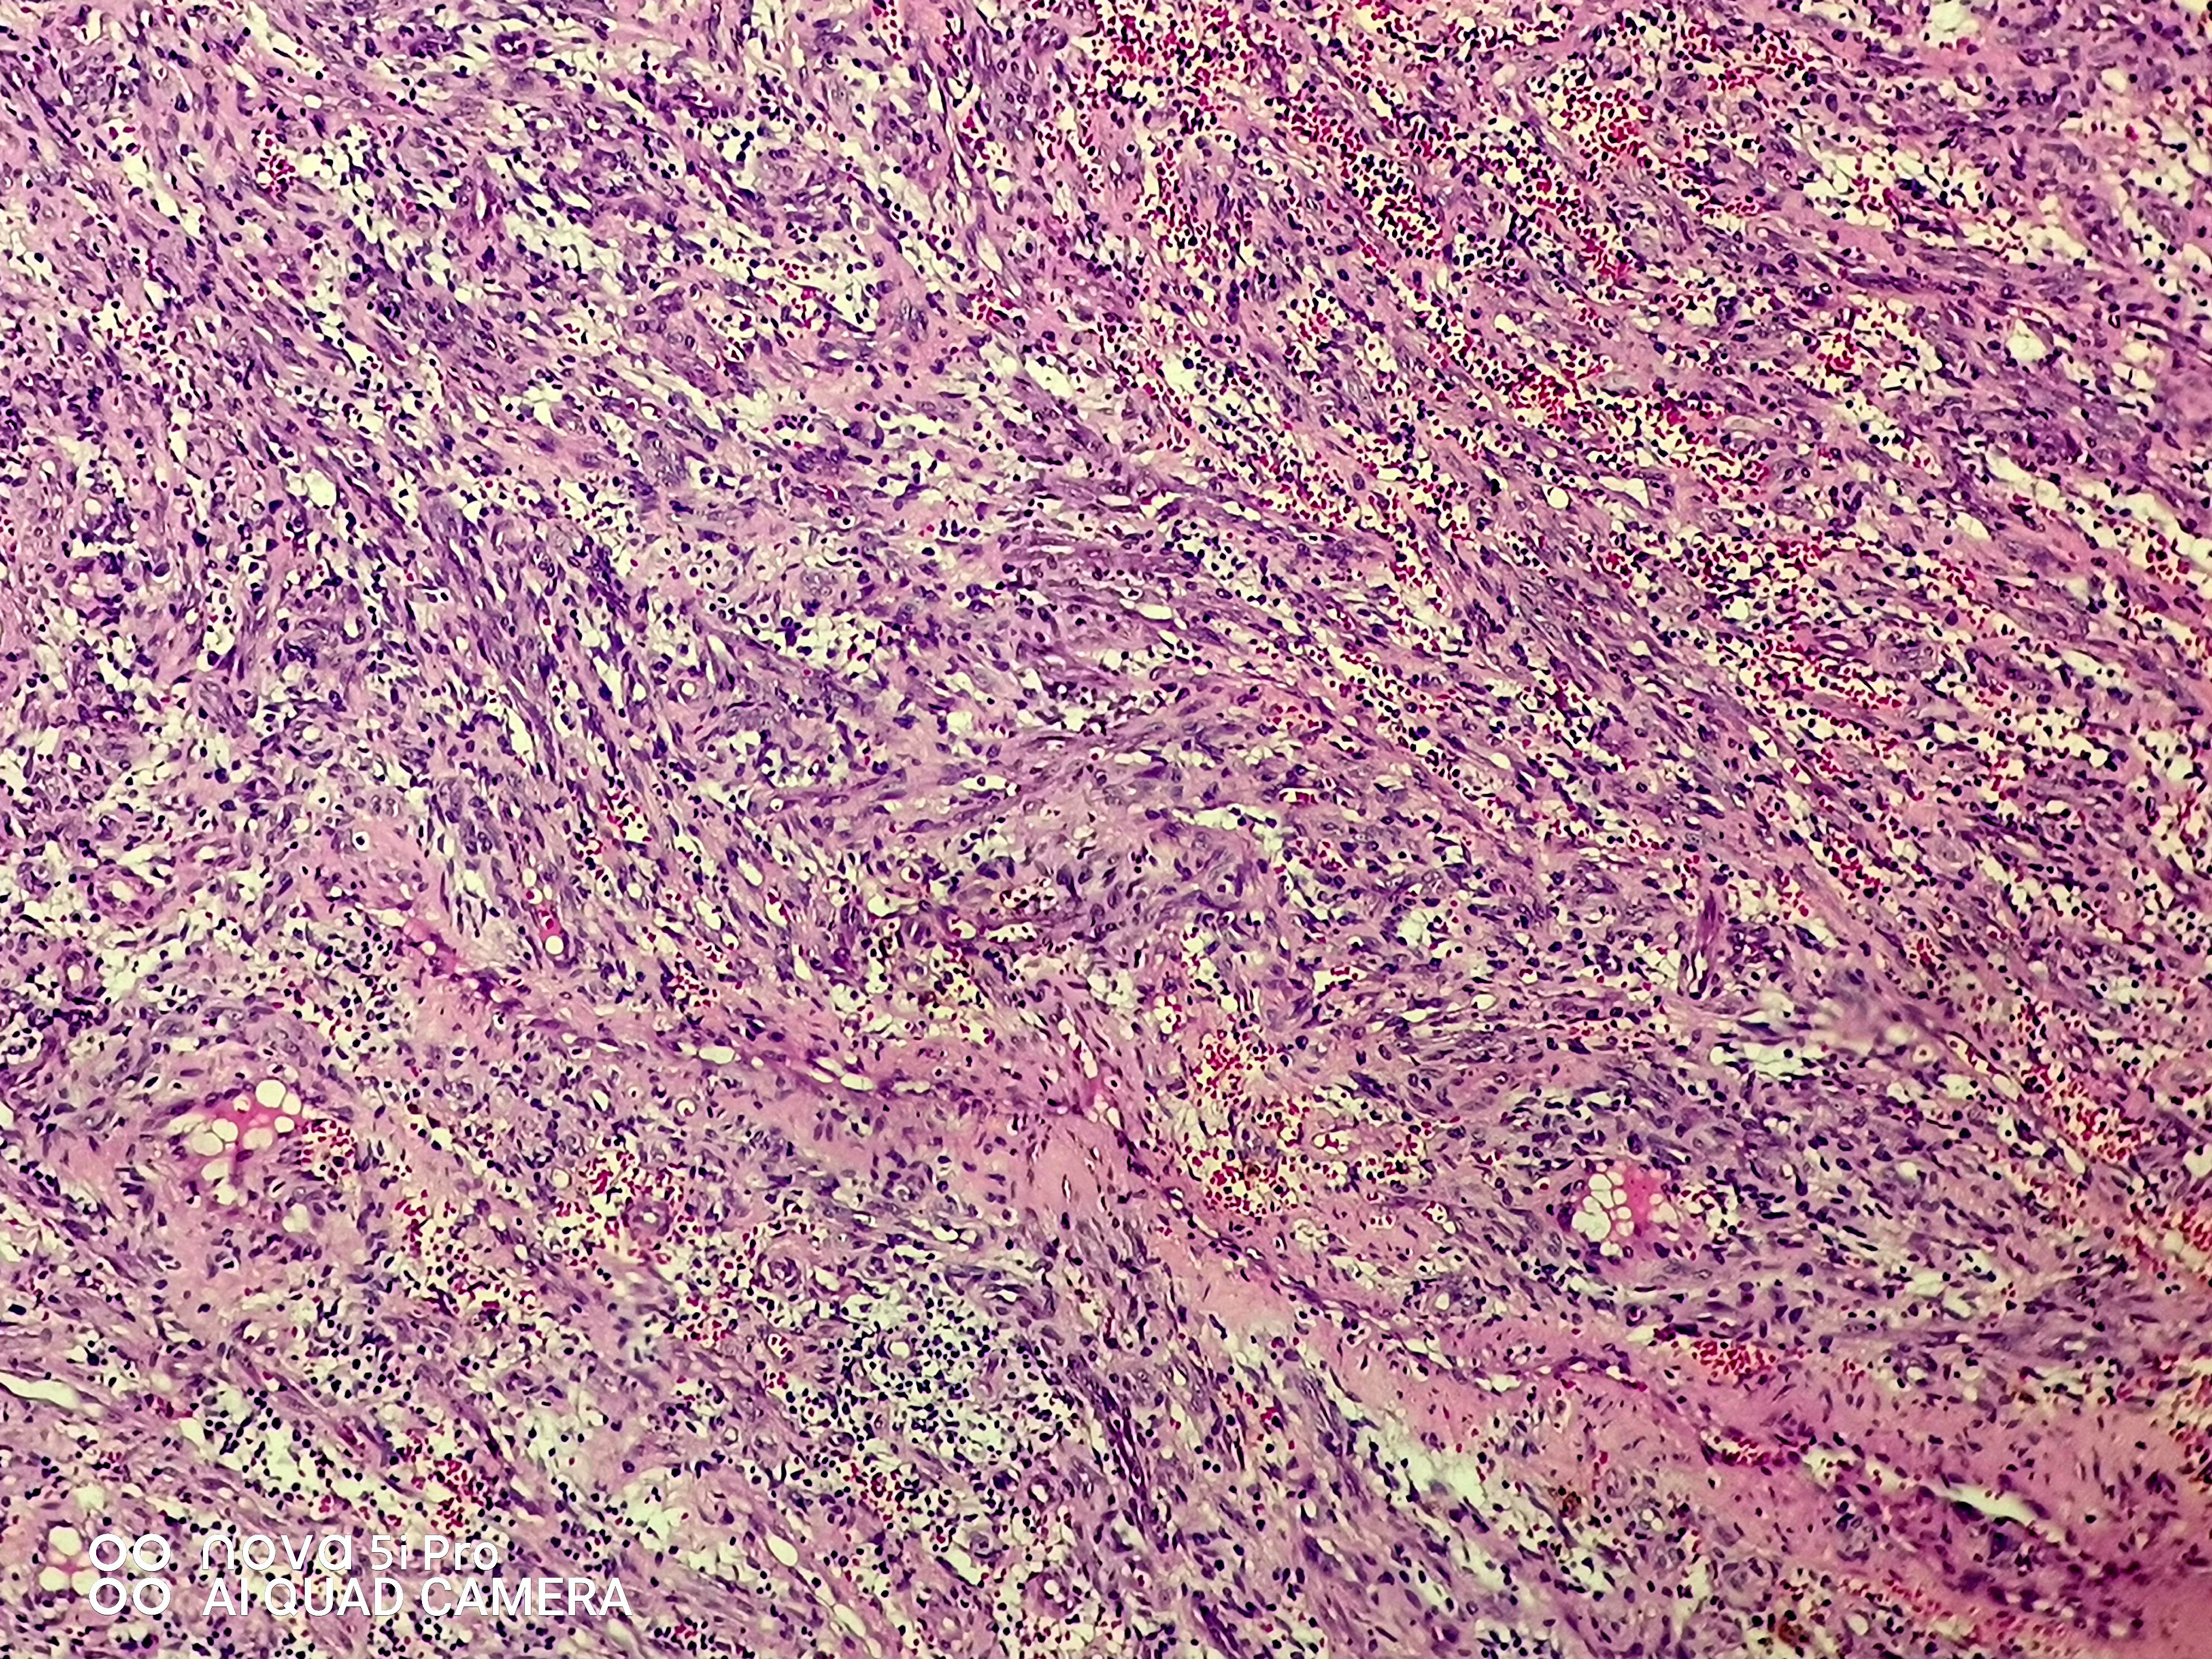

请老师们看看这个足跟肿块,血管瘤?谢谢了!

性别

女

年龄

43岁

临床诊断

待查

一般病史

发现左足跟肿块一年余

标本名称

左足跟肿块

大体所见

组织一块,大小约1.6*1.0*0.6cm,切开,实性灰白夹褐质中,一盒全取。

肉芽肿性毛细血管瘤。